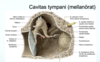

Nerven går in genom Porus acusticus int. och Meatus acusticus int. för att sedan komma in i Os temporale (pars petrosa). Härifrån kommer nerven sedan att löpa inferiort, genom Canalis nervi facialis och avger N. petrosus maj. et min. (vid Ganglion geniculi). Den fortsätter genom kanalen och avger även N. stapedius och Chorda tympani. Efter utlopp ur Foramen stylomastoideum avger den även grenar som försörjer M. digastricus venter post. (R. digastricus) och M. stylohyoideus (R. stylohyoideus) samt N. auricularis post. Nerven löper därefter framåt, igenom Gl. parotidea och delar upp sig i de ytligt belägna slutgrenarna som sprids solfjäderformat över ansiktet.